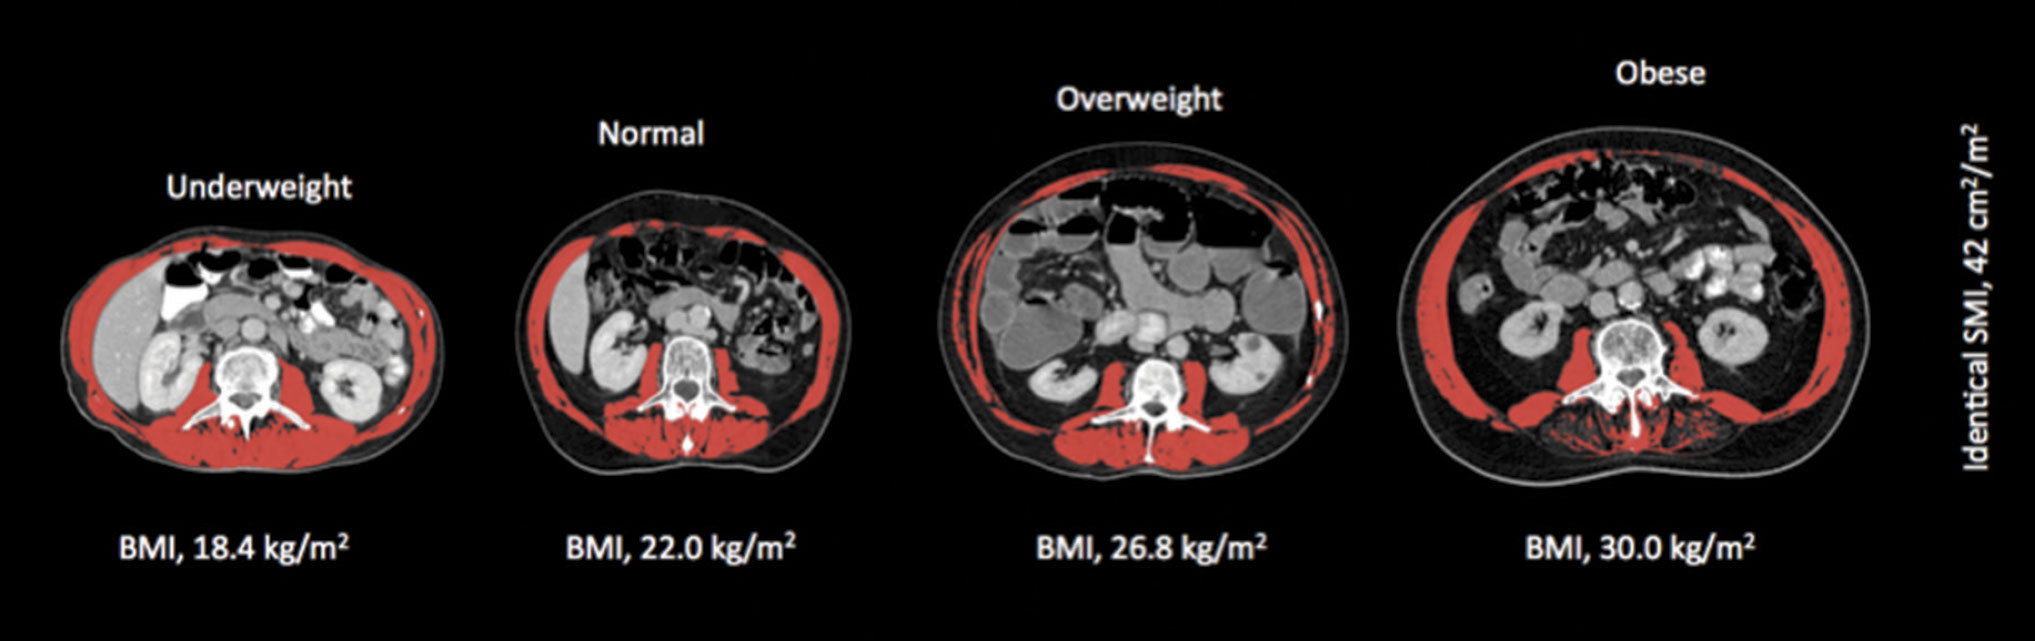

Figure 1A. Shows the variation in fat mass and body mass index (BMI) for four males with identical amounts of skeletal muscle

Figure 1A. Shows the variation in fat mass and body mass index (BMI) for four males with identical amounts of skeletal muscle(click to enlarge)

While the majority of cancer patients present with involuntary weight loss at the time of diagnosis,2 in the era of obesity cancer patients may not ‘look’ malnourished, with recent studies reporting that 40-60% are overweight or obese, even in the setting of metastatic disease.2,22,23,24 As the most clinically relevant phenotypic feature of cancer cachexia is muscle loss, identifying those with muscle loss becomes a huge challenge in overweight and obese patients as the loss of muscle is masked by excessive adiposity.

Sarcopenia

Sarcopenia comes from the Greek ‘sarx’ for flesh and ‘penia’ for loss, and is defined as ‘the age-associated loss of skeletal muscle mass and function’, often described as a muscle mass two standard deviations below normal.25 The best way to diagnose sarcopenia is by direct measurement of lean mass by DXA or CT. Despite the presence of high BMI in cancer patients, sarcopenia is present in 20-70% depending on the tumour type. Cancer patients with sarcopenia have a poor prognosis regardless of overall body weight.24 Recently it has emerged that the co-existence of obesity and sarcopenia is the worst-case scenario.26

As discussed previously, an additional challenge for cancer care providers is the fact that sarcopenia is a phenomenon that may be obscured within the bulk of body weight and body weight change and this is now recognised as a clinically important phenomenon.

Levels of malnutrition in 2015 are similar to those reported  more than 35 years ago, but today less than 7% of cancer patients are underweight (BMI < 18.5 kg/m2). The majority ‘look’ normal and 40-63% are overweight or obese. However, cachexia and sarcopenia are highly prevalent across all BMI categories with approximately one-third of obese cancer patients meeting the criteria for cachexia and 17-19% meeting criteria for sarcopenia. Cachexia and sarcopenia impact significantly on patients’ quality of life, tolerance to chemotherapy and survival.